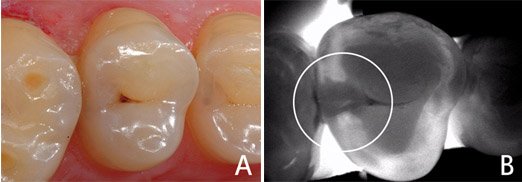

Пришло время поговорить о самом коварном виде кариеса, или скрытом - это кариес между зубами, возникающий при неудовлетворительной гигиене по причине неиспользования зубной нити/ершиков.

Пациент может думать до последнего, что с зубами все хорошо, пока однажды во время жевания жевательная эмаль попросту не проваливается и не оголяется полость, которая росла годами.

Зачастую страдают сразу оба зуба. Но не потому, что кариес заразная болезнь, хотя с натяжкой можно дать такую характеристику, а потому, что между зубами появляются максимально благоприятные условия для его развития.

Напоминаю - углеводы, бактерии и время. Из-за длительного игнорирования зубной нити в межзубные пространства попадают остатки пищи, которые находятся там очень долго, моментально создавая среду для размножения бактерий.

Бактерии перерабатывают углеводы в кислоты, которые забирают микроэлементы из эмали, и вуаля - возникает пятно, а затем все стадии кариеса по глубине поражения. Стоит отметить, что на контактах эмаль по анатомии тоньше и кариес быстрее попадает в дентин.

Как итог, кариесы на контактной поверхности - самые частые претенденты на вскрытие полости нерва и удаление этих самых нервов.